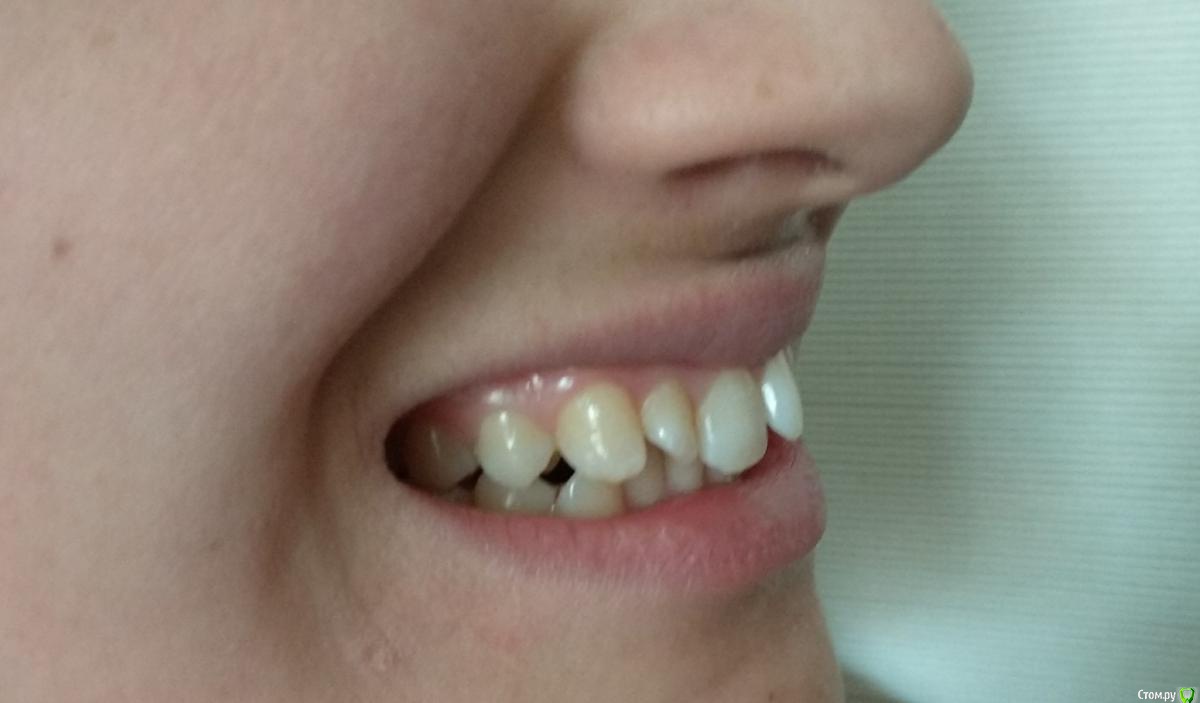

Гелла Опубликовано 15 апреля, 2018 Поделиться Опубликовано 15 апреля, 2018 Возможно ли ортодонтическое лечение без удаления зубов или с минимальным удалением (можно ли ограничиться только нижними восмерками)? Ссылка на комментарий

Monkey Опубликовано 20 апреля, 2018 Поделиться Опубликовано 20 апреля, 2018 Возможно ли ортодонтическое лечение без удаления зубов или с минимальным удалением (можно ли ограничиться только нижними восмерками)? Если лечение будет проводиться без удаления премоляров (а удалять их крайне нежелательно), то удаление верхних и нижних зубов мудрости необходимо. Ссылка на комментарий